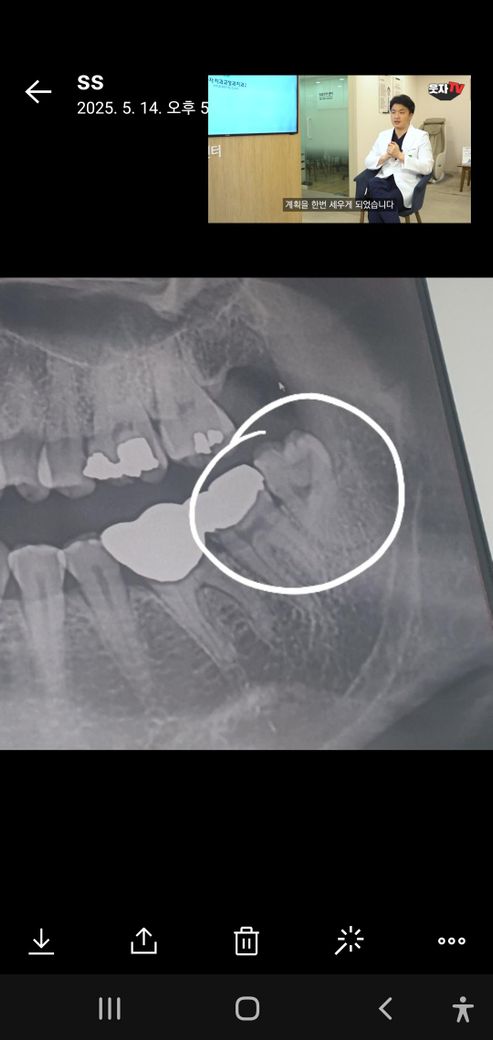

제 사랑니 종류는 무엇인가요? 반매복인가요? 수직매복인가요?..난이도는 어떻게보시나요? 뿌리가많이 휘었나요? 통증은 없고 가끔찬거먹음시린데 많이썩었다하네요..ㅜ 발치시간이 한몇분정도걸릴까요?

사진상으로 정확하진 않지만 저정도 상태라면 부분 매복상태라고 봐야되지 않을까 생각됩니다.

1. 반매복 정도라고 보시면 됩니다

2. 뿌리가 약간 휘어있지만 높은 난이도는 아닙니다

3. 충치가 있는 사랑니는 뽑는데 좀 시간이 걸릴수도 있습니다